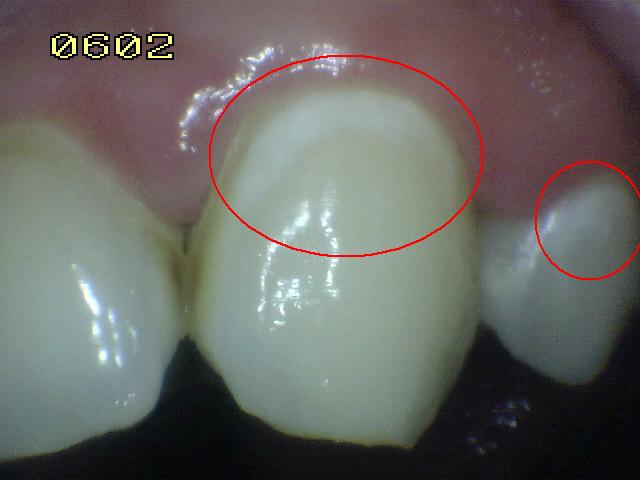

Código 3